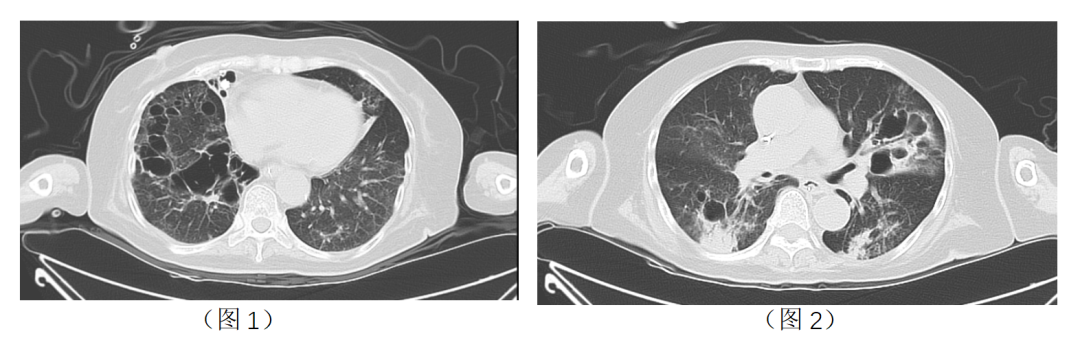

2023-2-8胸部CT:(见图1、图2)

• 考虑双肺感染,多发脓肿及空洞形成,支气管扩张。

• 对比2023-01-30胸部CT,部分空洞较前稍缩小,余大致同前